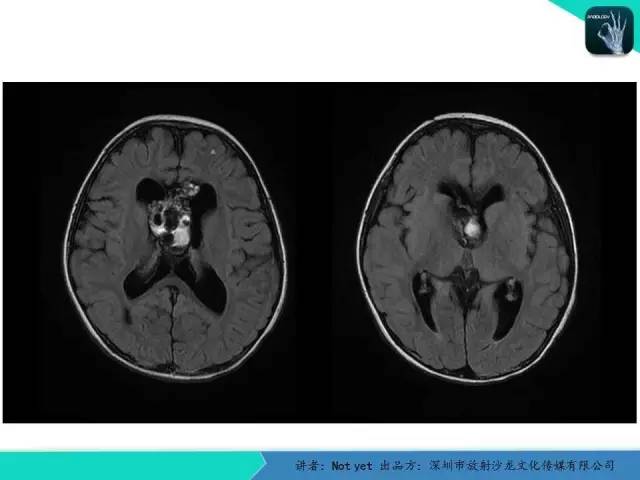

【病例】脑室内脉管瘤1例CT及MR影像诊断与鉴别